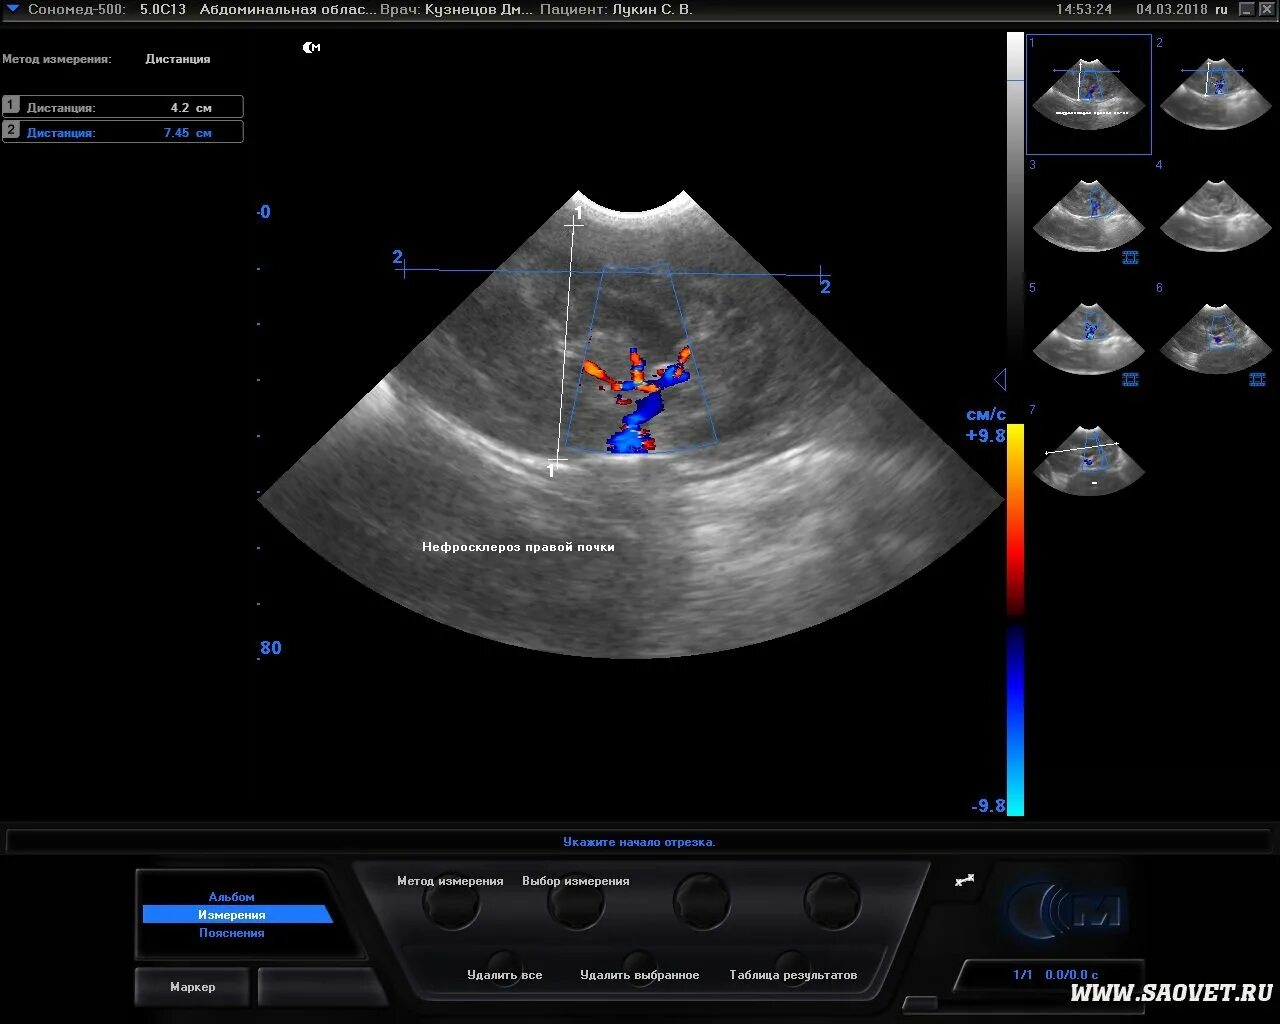

Нефросклероз почек на узи что это такое